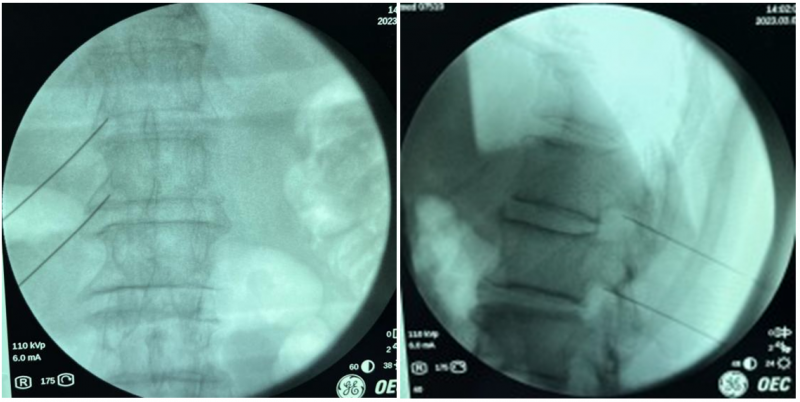

73岁的刘大爷是一位肺癌患者,自从去年11月查出肺部肿瘤之后一直坚持治疗,精神状态及生活质量均与常人无异。然而就在1个月前,他开始感到左侧睾丸疼痛,并且伴有左下腹部的撕扯放射痛,服用强效止痛药,疼痛非但没有缓解,反而逐日加重,以至于彻夜难眠,严重影响着他的生活质量。刘大爷不得已来到医院,在接受相关检查后发现多发脏器转移灶,但没有找到疼痛直接原因。转到疼痛科后,通过胸腰段磁共振检查找到了疼痛的罪魁祸首,原来是刘大爷体内的肿瘤进展并出现了第十二胸椎左侧横突部的转移。

image001.jpg

通过胸腰段磁共振检查,找到引发患者痛疼的原因。